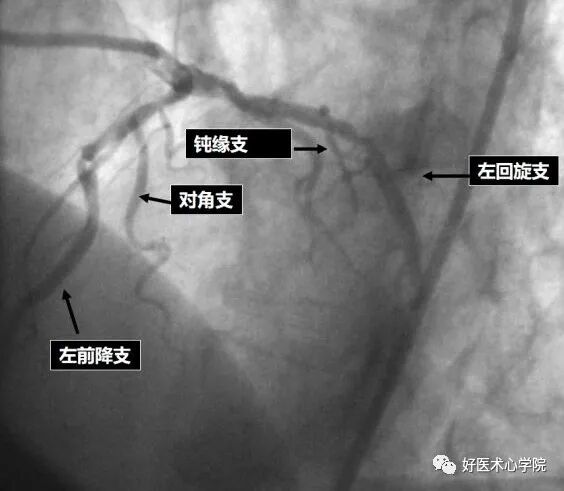

分支辨别